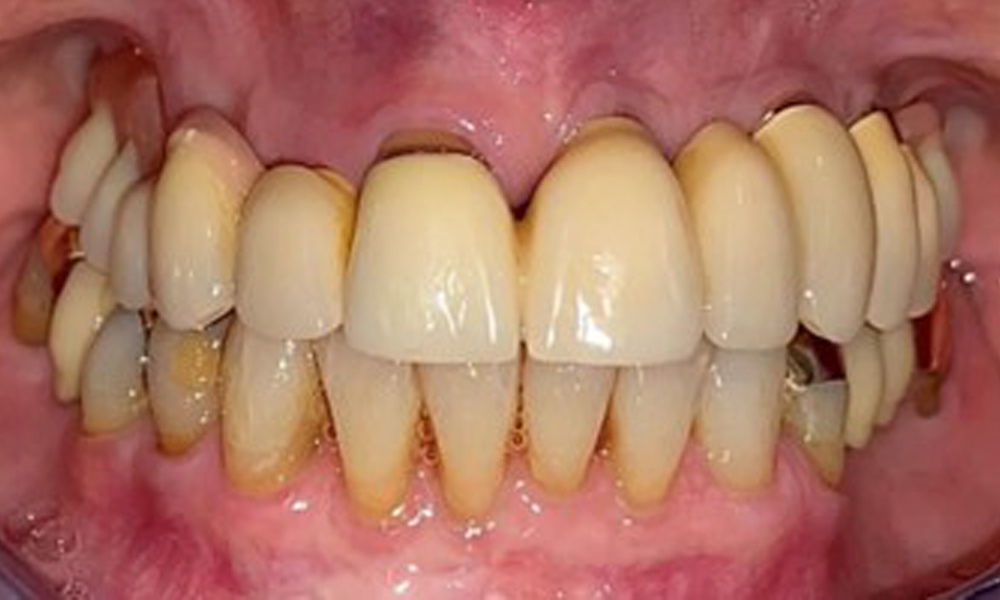

The patient was fitted with a combined removable maxillary telescopic prosthesis more than 25 years ago (Fig. 1, Fig. 2, Fig. 3) and is very happy with her dentures. The patient has an adequate fixed denture for the mandible (Fig. 4).

The dental findings are as follows: Combined removable implant and tooth-supported telescopic prostheses on implants 15, 13, 21, 23, 24, 25 and tooth 11 (Fig. 1, Fig. 2, Fig. 3). The patient was fitted with a fixed mandibular denture. Adequate bridges were present over 37 to 34 and 45 to 47 (Fig. 4), the crown margins were intact and there were no active caries. A composite filling with a marginal gap was present on tooth 43. There was mandibular gingival recession, exposing 1 to 3 mm of root surface. This also applies to 11.